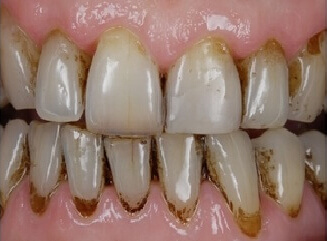

Проблема. На поверхности зубов виден зубной налёт.

Решение. В ходе процедуры с поверхности зубов удаляется зубной налёт с помощью ультразвукового скалера и содоструйного аппарата (Air Flow). В конце процедуры зубы полируются.